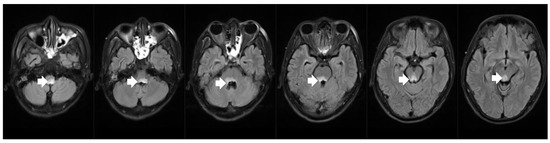

As for laboratory examinations, positive serological results included elevated anti-aquaporin-4 antibody and anti-SS-A antibody (+++) levels. CSF examination showed normal cell count and protein values. Cardiac ultrasound, EEG, and abdominal imaging with contrast-enhanced CT did not confirm any abnormalities. However, a high-intensity lesion was found in the dorsal part of the medulla oblongata in brain MRI (Figure 2). The patient was diagnosed with NMOSD accompanied by SSS and Sjögren syndrome. His SSS was cured, followed by the disappearance of the hiccups and vomiting, after he was treated with intravenous IVIG (0.4 g/kg × d × 5 days) and methylprednisolone (1000 mg/d × 5 days). In addition, both his heart rate and blood pressure stabilized at around 70 bpm and 100/60 mmHg, respectively, after the temporary pacemaker was removed. He had no neurological or cardiac sequelae after the initiation of immunotherapy. After discharge, the patient gradually reduced and then stopped his intake of oral steroids and started using Rituximab as a disease-modifying therapy. The patient’s condition remained stable with no relapses.

Figure 2.

Brain MRI revealed bilateral high-intensity lesions in the dorsal part of the medulla oblongata on axial fluid attenuated inversion recovery (FLAIR) sequence.